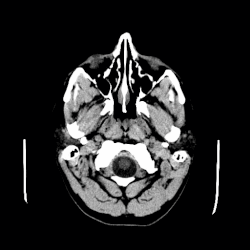

Коллоидные кисты можно диагностировать по представленным симптомам. Требуется дополнительное обследование и дифференцирование. МРТ и КТ часто используются для подтверждения диагноза.[5]